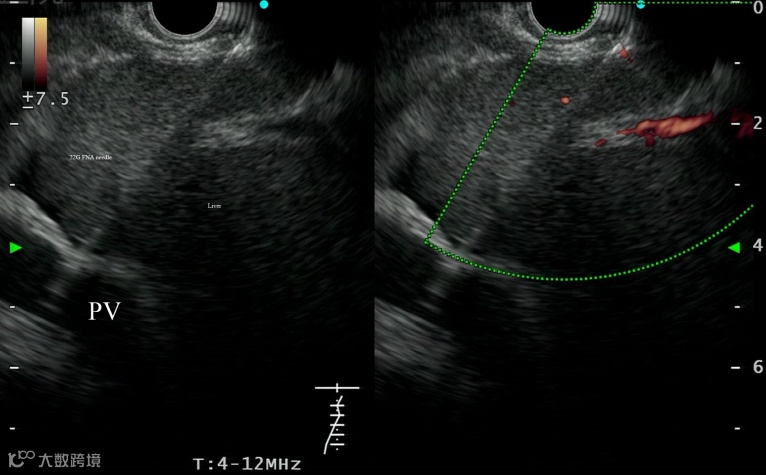

超声内镜(EUS)引导下门静脉压力梯度(PPG)测量是一种评估门静脉高压严重程度的新方法。近日,来自我国南京大学医学院附属鼓楼医院的Zhang W等人研究了急性或亚急性门静脉高压患者EUS-PPG与肝静脉压力梯度(HVPG)测量值间的一致性。相关内容发表在Gastrointestinal Endoscopy杂志上。

该前瞻性研究共纳入12例患者。使用22号细针抽吸针(FNA)在EUS引导下行PPG中央静脉压测量。采用经颈静脉入路测量HVPG。如果无法获得HVPG测量值,并且患者接受了经颈静脉肝内门体分流术(TIPS)治疗,则在手术过程中记录PPG作为参考标准。最后评估EUS引导下PPG的可行性与安全性,并分析两种测量方法之间的相关性。

结果发现,EUS-PPG成功测量11例(91.7%)。在2例Budd-Chiari综合征(肝静脉阻塞亚型)患者中HVPG测量失败,其中1例接受TIPS并获得经颈静脉PPG数据。在一次HVPG测量中发现一个小分流导致测定不准确。最终,9例患者纳入统计分析。患者平均EUS-PPG和HVPG/PPG(经颈静脉)分别为18.07±4.32 mmHg和18.82±3.43 mmHg。两种方法间的Pearson相关系数为0.923(P<0.001)。

因此,EUS引导下用22号细针测量门静脉压力是一种安全、准确的方法,有望作为检测HVPG的补充方法。

本项来自南京鼓楼医院的研究发现,针对急性或亚急性门静脉高压患者,EUS引导下测量的PPG与在介入条件下测量的HVPG/PPG具有良好的相关性(R=0.923,P<0.001)。研究从2018年6月到2019年12月连续入组了12位患者,其中1例患者EUS-PPG测量失败,另外两位患者HVPG测量失败,最终纳入分析的患者为9人。结果表明,EUS-PPG与介入条件下测量的HVPG/PPG的测量值(18.07±4.32 mmHg vs. 18.82±3.43 mmHg, P=0.231)及手术时间(38.33±15.41 s vs. 37.22±6.18 s, P=0.862)无显著性差异。

本研究设计看似简单,但实施难度不小,如:EUS引导下的血管穿刺、具有配对的EUS-PPG和HVPG。作为发表在国际内镜顶刊Gastrointestinal Endoscopy的数据,该研究借助EUS新技术测量PPG,可在一定程度上解决HVPG检测技术人员短缺、仅能评估窦性肝硬化门静脉压力等问题。本研究作者团队提到:①该研究结果仍需要大样本的验证;②深度镇静药物可能影响EUS-PPG测量的准确性(Liver Int 2014)。因此,适度镇静和镇痛对于此类患者是否更加合适?CHESS正在进行的另一项研究试图探索适度镇静和镇痛对HVPG检测准确性的影响。